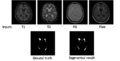

Since winter project week in Utah, we have developed/implemented a WML segmentation algorithm using ITK classes. Subtasks implemented include: (1) a skull stripping algorithm working on T1 weighted images; (2) a fuzzy clustering algorithm for tissue segmentation; (3) a parametric model for gain field correction. All of these subtasks are implemented by using ITK. The training step uses AdaBoost and the segmenation step uses a support vector machine.